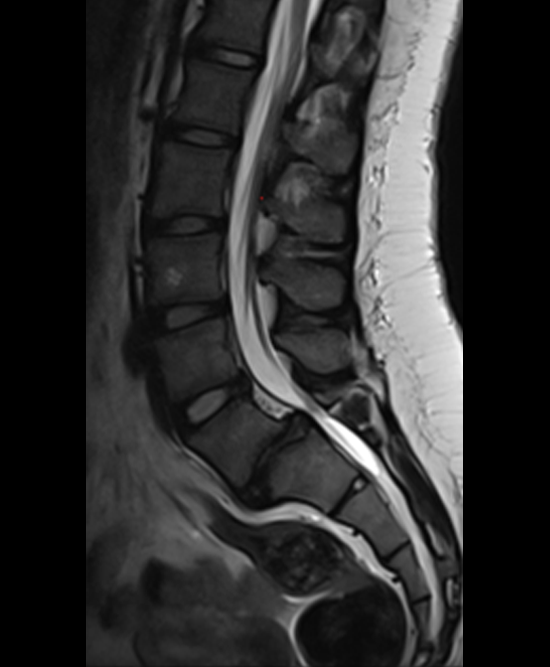

A 17-year-old girl presented to the spine clinic with significant low back pain. X-ray, CT and MRI imaging (Figs 1-3) showed evidence of spondylolisthesis. Upon clinical examination of spinal alignment, the patient was found to have a pelvic incidence of 78°, a lumbar lordosis of 54°, and a pelvic tilt of 51°.